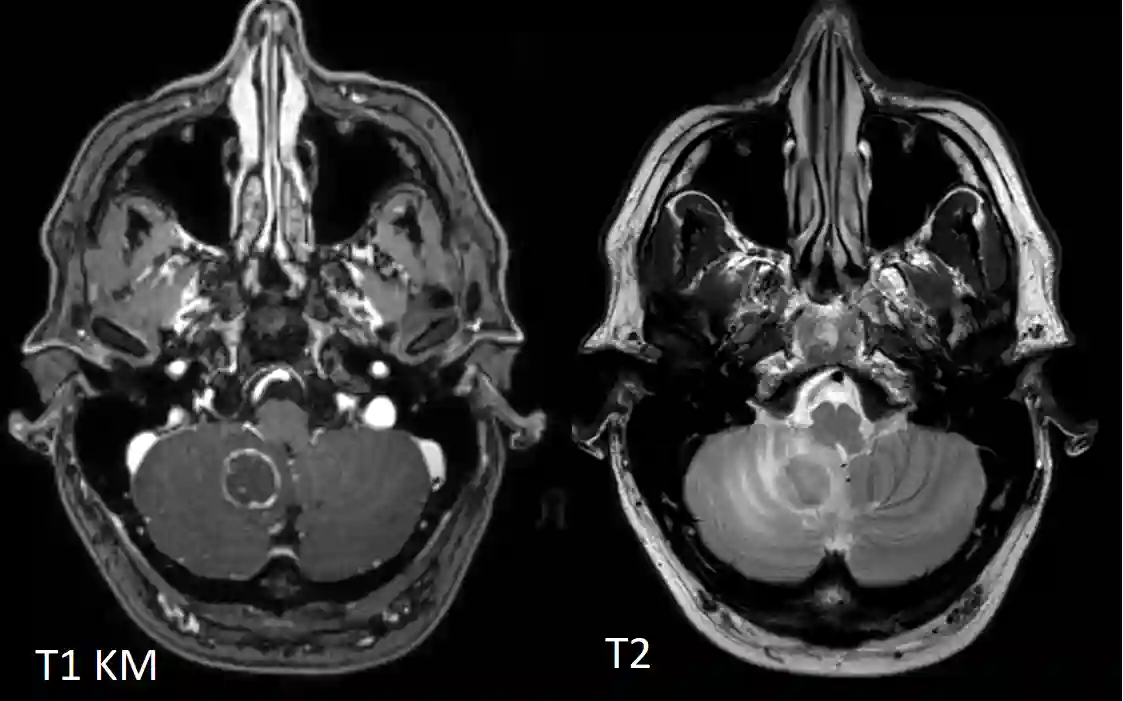

In der CT und MRT Bildgebung zeigen einzelne oder mehrere Läsionen mit ringförmiger Kontrastmittelaufnahme, die später verkalken können2.

Cerebelläre Neurotoxoplasmose MRT

MRT Bildgebung eines Patienten mit einer bestätigen Neurotoxoplasmose. Axiale T2 Sequenz und T1 Sequenz mit Kontrastmittel.